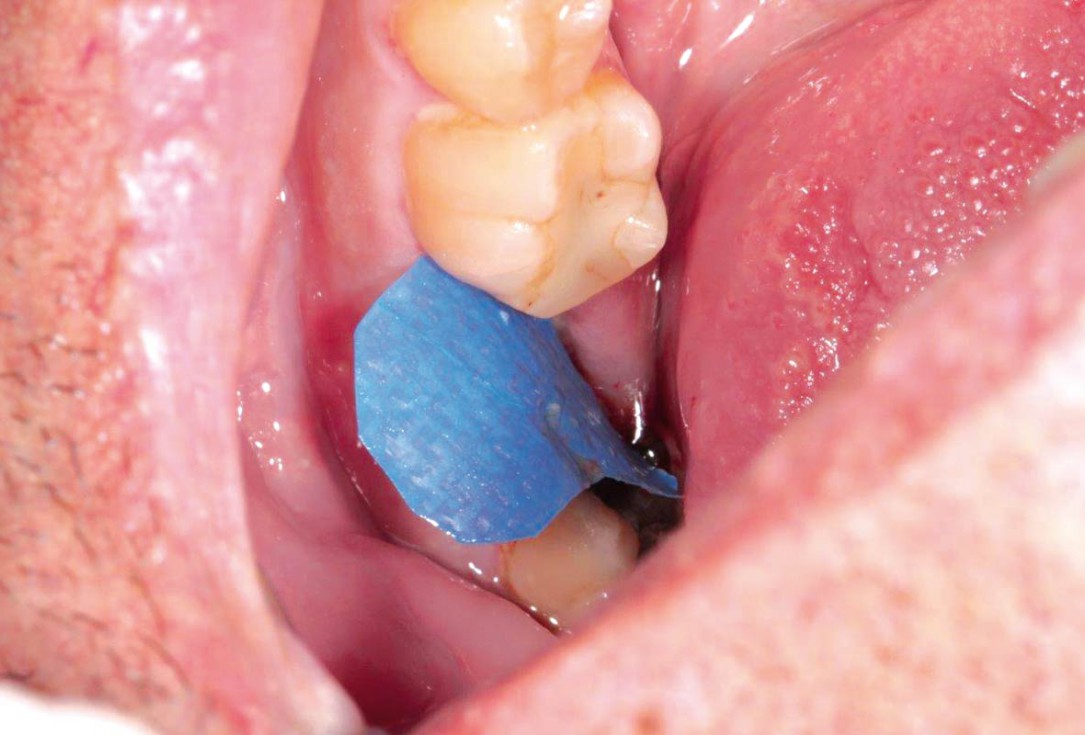

botiss cerabone® & collagen fleece for immediate implantation - Clinical case by Dr. D. Jelušić

Clinical situation before extraction and implantation